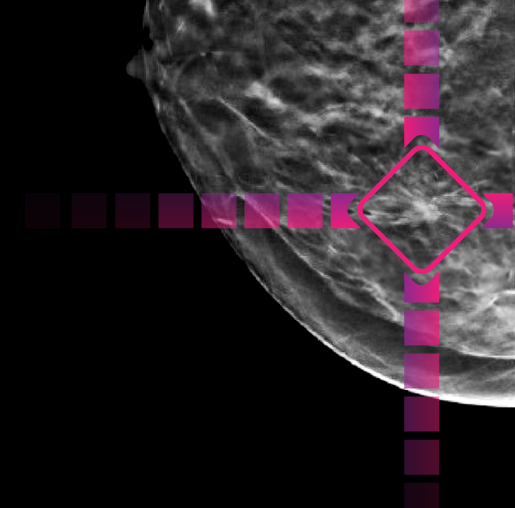

The Enhanced Breast Cancer DetectionTM (EBCDTM) program is a breakthrough in early detection. It uses artificial intelligence to help radiologists detect even subtle lesions. Combined with exceptionally high-quality mammography systems, EBCD's artificial intelligence (AI) optimizes breast cancer screening, giving women greater confidence in their results.

Step 2: AI-assisted breast cancer detection

The AI points out areas of interest on your exam to help the radiologist detect very subtle abnormalities.